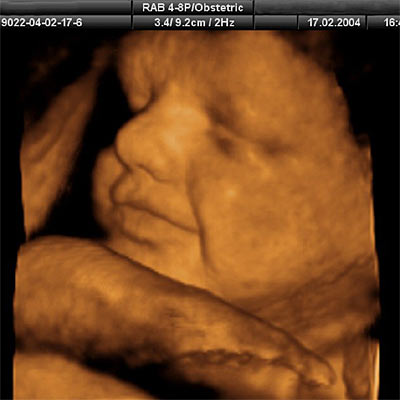

Las imágenes son tan bellas y reales que parece que han logrado meter una cámara en el útero. Pero su realización ha sido posible gracias al empleo de las últimas tecnologías de imágenes ultrasónicas en tres y cuatro dimensiones (3D y 4D), que ofrecen una fotografía nítida y secuencias en movimiento a tiempo real. A estos fotogramas se unen recreaciones hechas por ordenador y además, han filmado, esta vez sí con una minicámara dentro del abdomen de la madre, una operación de un embarazo complicado.

La cinta incluye las reacciones del feto a ciertos estímulos, así como sus diferentes comportamientos y su propia preparación para el parto. Así, entre las aportaciones del documental están imágenes escaneadas en 4D de un feto de entre 11 y 12 semanas que se golpea y mueve las piernas en una especie de acto reflejo; a las 24 semanas, el feto ya abre y cierra los ojos, saca la lengua y muestra sus primeras expresiones faciales. También experimenta su primer ataque de hipo, con fuertes contracciones del diafragma.